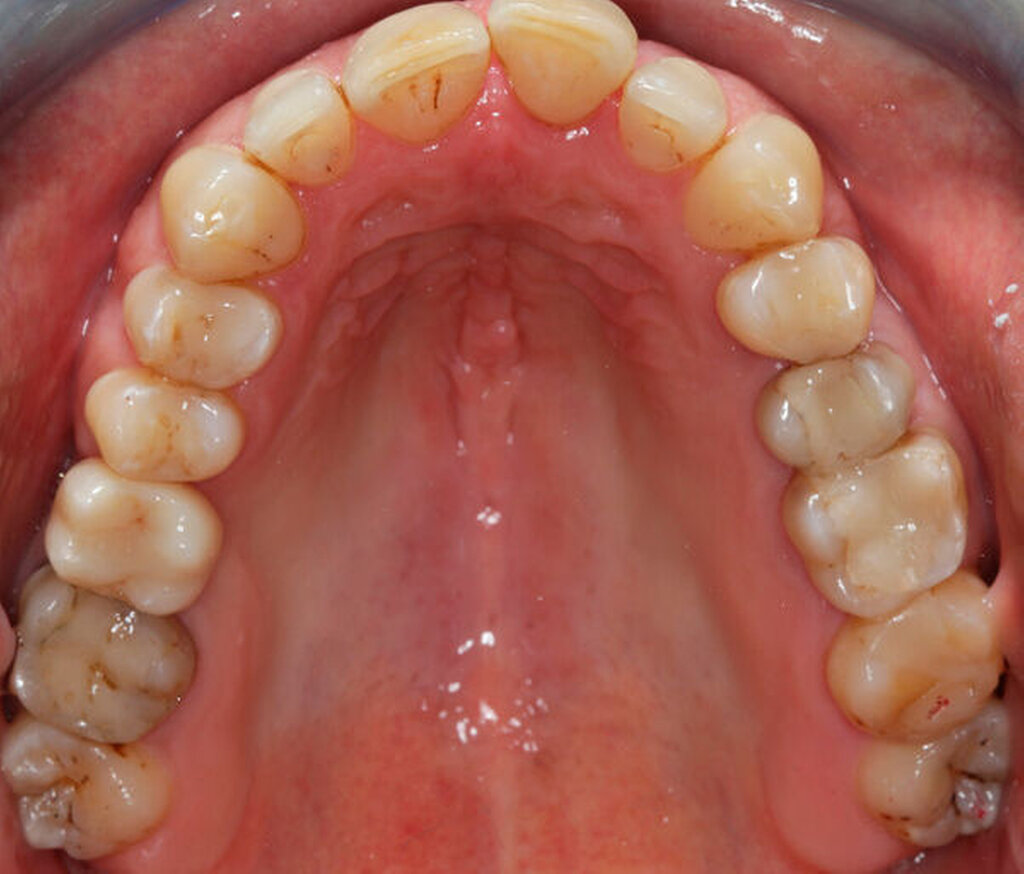

Das Fallbeispiel beschreibt das Vorgehen bei einem 38-jährigen, gesunden Patienten mit einer Einzelzahnlücke in Regio 16 (Abbildung 1). Laut Anamnese lagen keine Kontraindikationen für eine Implantation vor. Es bestand eine suffiziente Mundhygiene. Alle notwendigen Vorbehandlungen waren abgeschlossen. Das Implantat konnte wie geplant inseriert und nach Abschluss einer dreimonatigen Einheilzeit mit einer transokklusal verschraubten monolithischen Keramikkrone aus Lithiumdisilikat versorgt werden. Seit der Implantation im Mai 2019 wurden keine Komplikationen dokumentiert.

Intraorale Ausgangssituation und Wax-up

Zunächst erfolgten analoge Abformungen mit Rim-Lock-Löffeln des zu implantierenden Oberkiefers (Vinylpolyethersilikon: EXA‘lence, GC Corporation, Tokio, Japan) und des Unterkiefers (Alginat rosa, Omnident Dental-Handelsgesellschaft mbH, Rodgau Nieder-Roden). Zur Kieferrelation wurde die habituelle Okklusion verschlüsselt (LuxaBite, DMG Chemisch-Pharmazeutische Fabrik GmbH, Hamburg). Das prothetische Ziel wurde mithilfe eines analogen und vom Oberkiefermodell abnehmbaren Wax-ups definiert. Dieses sollte in seiner Ausdehnung und Funktion der zukünftigen implantatgetragenen Versorgung entsprechen und für die Planung genutzt werden können. Für das Backward-Planning wurden die Modelle und das Wax-up mithilfe eines Laborscanners (D2000, 3Shape A/S, Kopenhagen, Dänemark) digitalisiert. Die Oberflächendaten wurden als STL-Datensätze exportiert, um diese später für die Erstellung eines virtuellen 3-D-Kiefers in einer IPS zu nutzen.